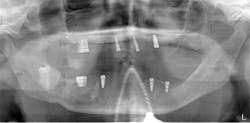

After the fabrication of full upper and lower immediate dentures, the patient underwent extraction of the remaining teeth and the placement of eight immediate dental implants (Hahn Tapered Implants, Glidewell; figure 8).

At one month, ISQ readings were taken of all the implants except No. 3. The lower arch showed the soft tissue healing at that time (figure 9). At 2.5 months, readings were taken again, and it was indicated that the mandibular arch had integrated and was ready for final attachment via locator attachments (Zest; figures 10 and 11). The maxillary implants were continuing to show progress, but not to the point where predictable loading was possible. Because the maxillary denture was stable (as most are), this was not an issue. The patient greatly appreciated the completion of the mandibular overdenture, which was very mobile and bothersome.

Figure 8: Post-op panorex

At 13 weeks, the maxillary implants were again tested, and they showed adequate stability to load (figure 12). The implant in the No. 3 position was exposed and ISQ-tested at this time. A 3 mm healing abutment was placed, and the soft tissue was allowed to heal for two weeks (figure 13) prior to placing final abutments and retrofitting the maxillary denture with locator housings.